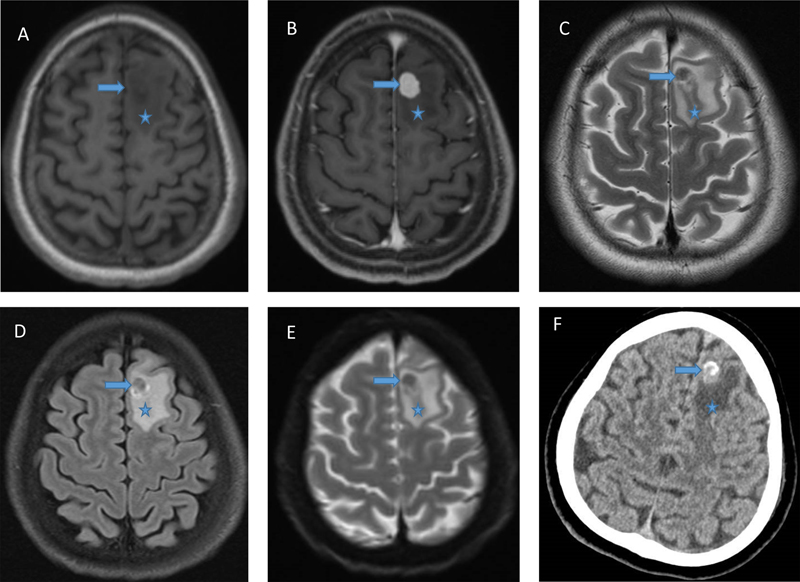

Head magnetic resonance imaging (MRI) showed an avidly enhancing well-circumscribed intra-axial nodule in the left superior frontal gyrus extending to cortex, measuring 1.2 x 0.8 x 1.2 cm, and surrounded by vasogenic edema. It was hypointense on T2-weighted sequence. Diffusion weighted imaging showed no diffusion restriction. There was no blooming on susceptibility-weighted image. Computed tomography (CT) scan showed calcification. The main concern was solitary brain metastasis. (Fig. 1)

Figure 1.

A. MRI: T1 showing circumscribed intra-axial nodule in the left superior frontal gyrus; B. MRI: T1 with gadolinium showing avid enhancing; C. MRI: T2 showing hypointensity of the lesion; D. MRI: FLAIR; E. MRI: Diffusion weighted imaging showing absence of diffusion restriction; F. CT scan with hyperdense areas construed as calcification by radiologists. In all images, arrow indicates tumor, and asterisk edema.